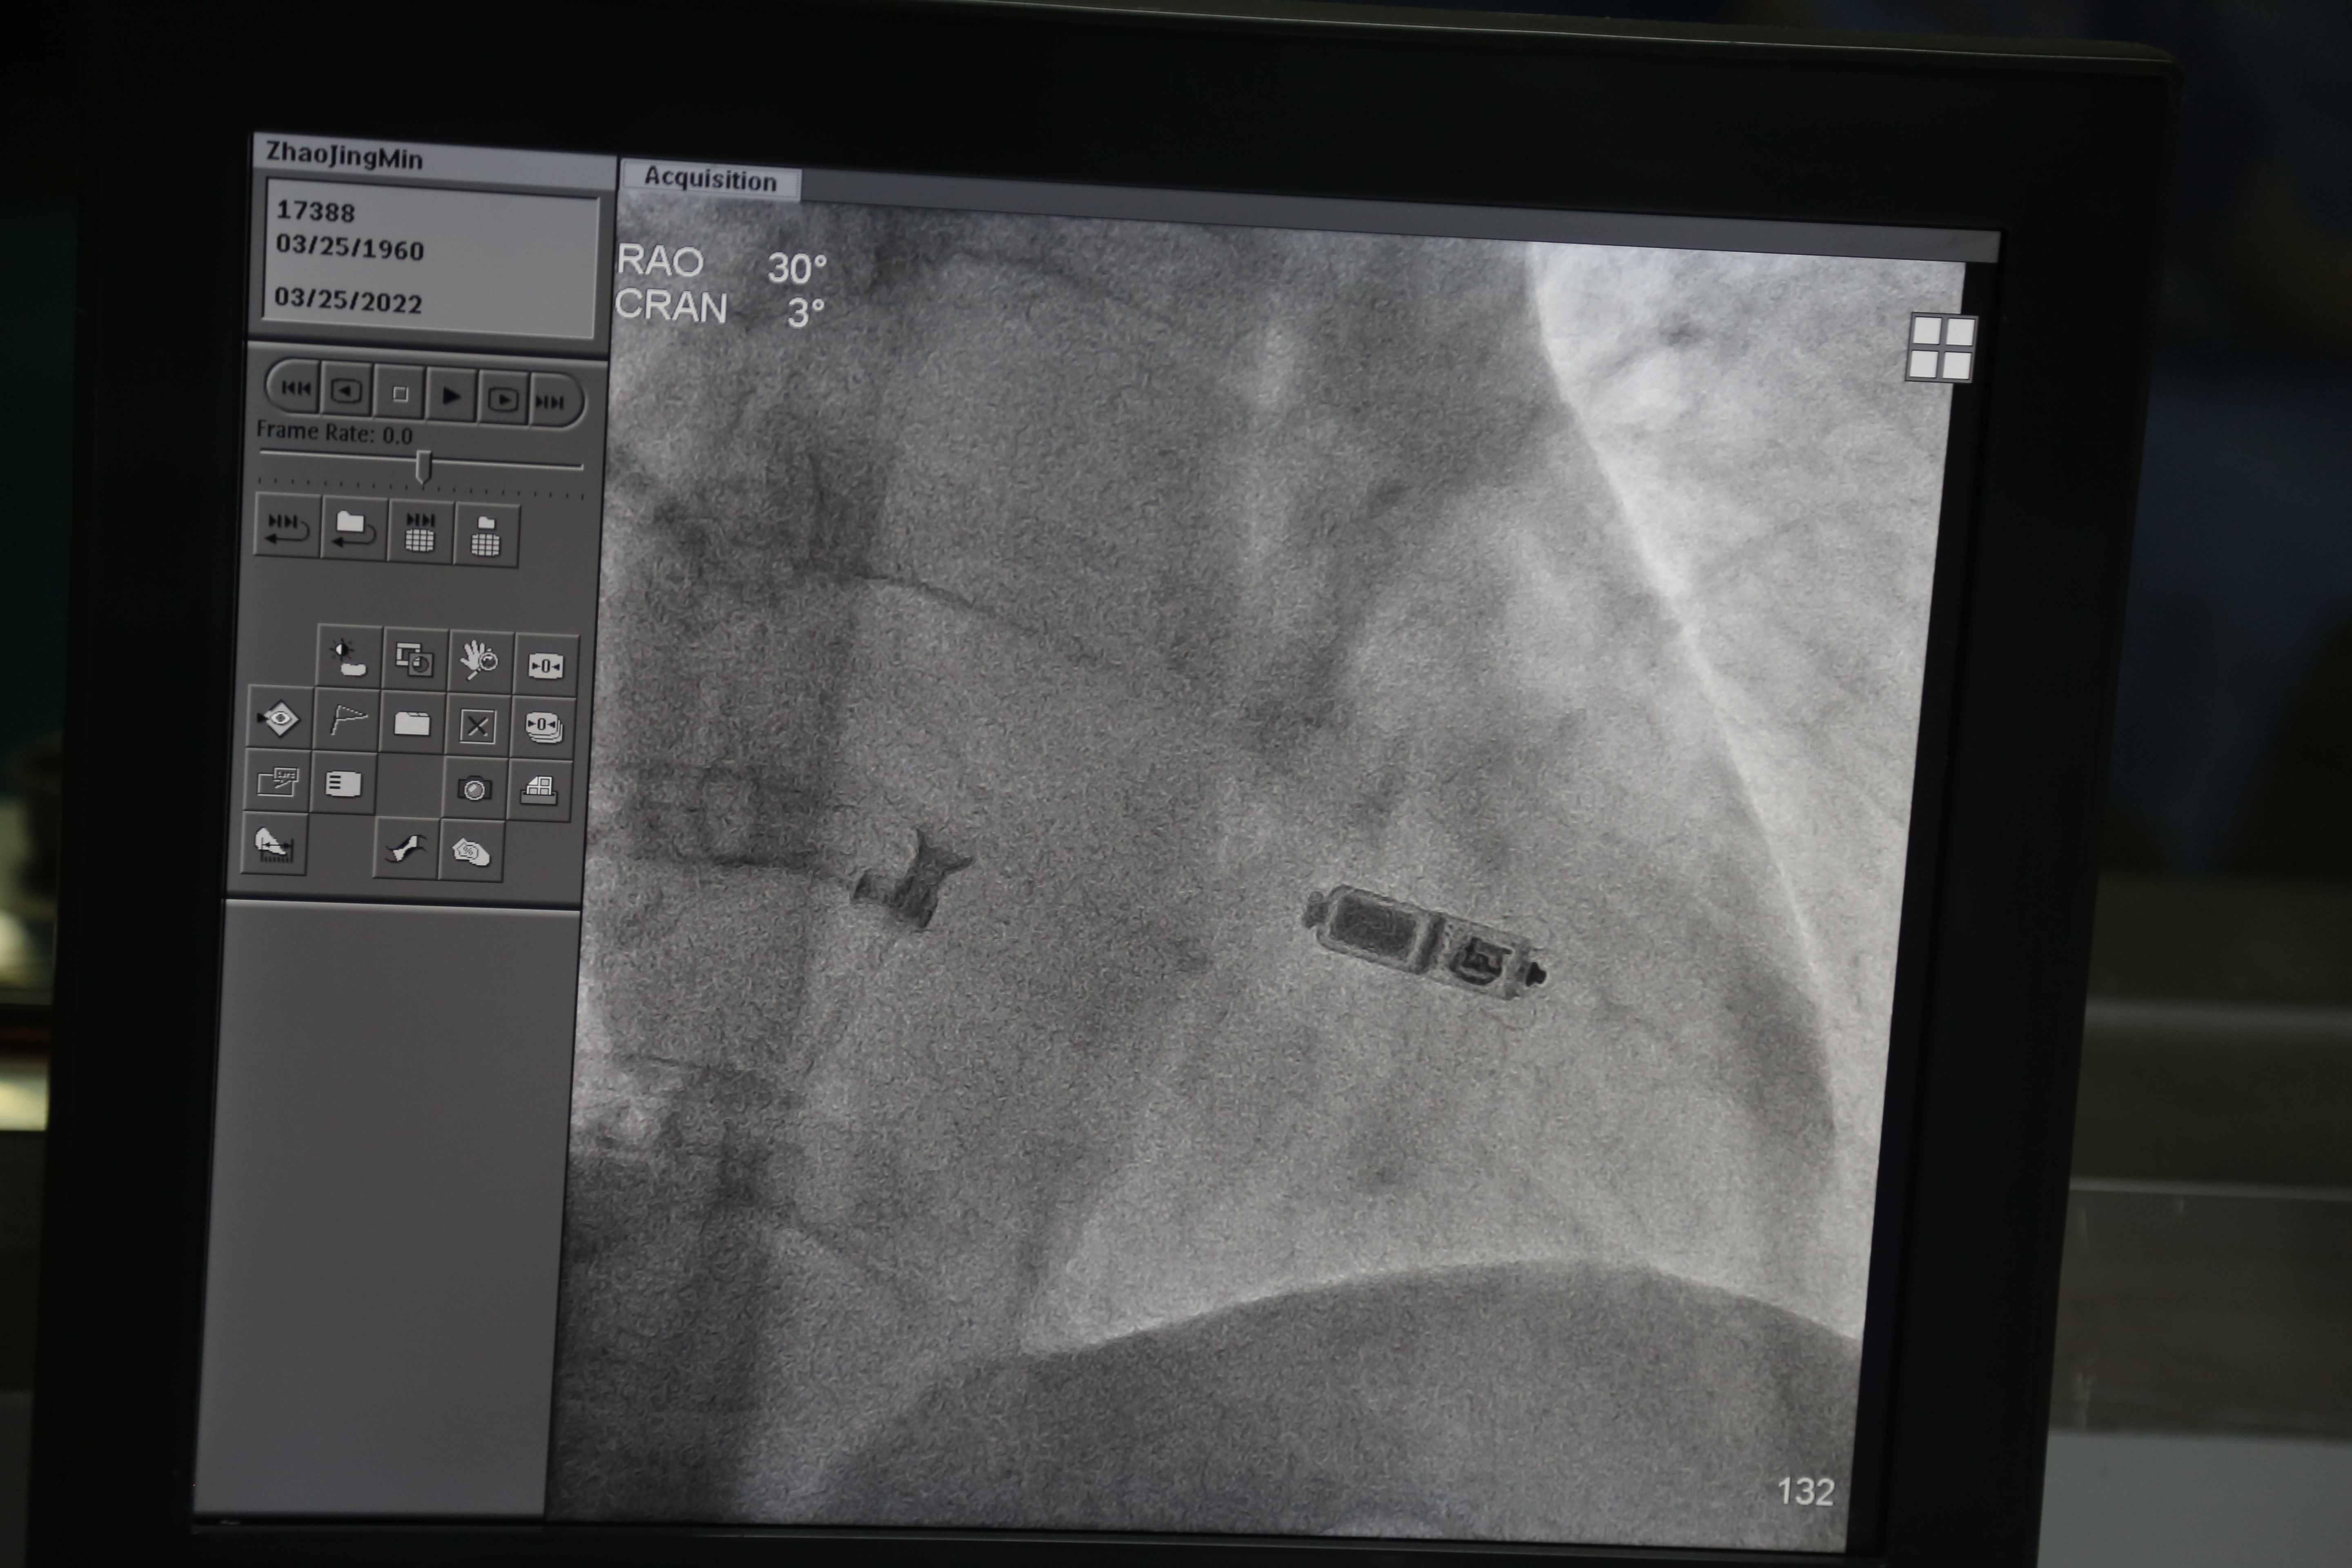

科技引领发展,技术造福患者。张俊岭带领院心脏中心房颤中心团队在局部麻醉下实施无导线心脏起搏器植入手术,患者全程清醒,因为心脏没有感觉神经,植入后患者完全感觉不到它的存在,活动不受限。在手术中,经右股静脉穿刺,常规操作后沿传送导管将无导线心脏起搏器递送系统送至患者的右心室,将递送系统头端置于右室心尖部,释放无导线心脏起搏器,行牵拉试验,多体位造影提示三个固定小翼与心肌组织啮合牢靠。手术完成后,经测试起搏器的电学参数,各项参数指标堪称完美,填补了衡水的一项医疗空白。张俊岭指出,无导线心脏起搏器适用于病态窦房结综合征、房室传导阻滞、房颤伴有心动过缓等,对高龄患者以及对生活质量有较高需求的爱美患者也特别适用,它的投用将大大改善患者的生活质量。